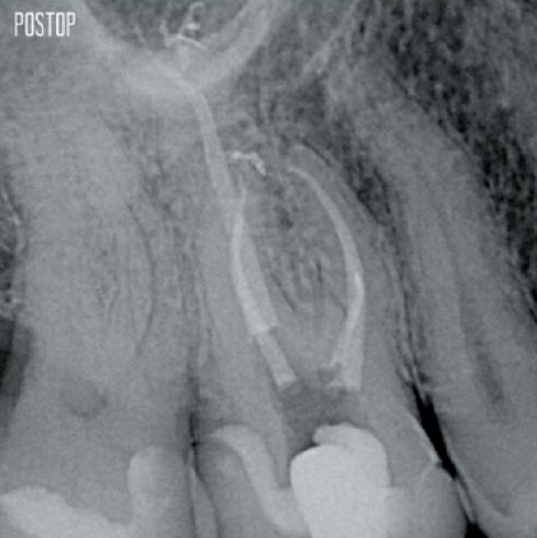

写真提供:Ahmed Salman医師

より多くの象牙質が保存されます。適切なシェーピング、洗浄、充填を確保します。